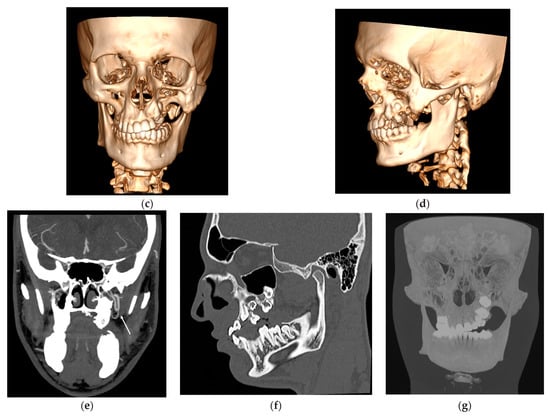

Figure 1.

Volume rendering (VR) reconstructions of soft-tissues (a,b) shows tumefaction of the left hemiface. Bone-based VR images (c,d) show hyperplasia of the left zygomatic bone and of the ipsilateral hemimandible including the condylar region. Loss of substance in the alveolar process of the left maxillary bone with ectopia of some dental elements, some of which are impacted, are also visible. Coronal maximum intensity projection (MIP) reconstruction (e) obtained after intravenous contrast medium injection better demonstrates the ectasia of the left pterygoid venous plexus (arrow). Bone-window sagittal-oblique image (f) and coronal MIP thick-slice reconstruction (g) demonstrate deformation of the left superior dental arch with some teeth retention but no bone erosion.